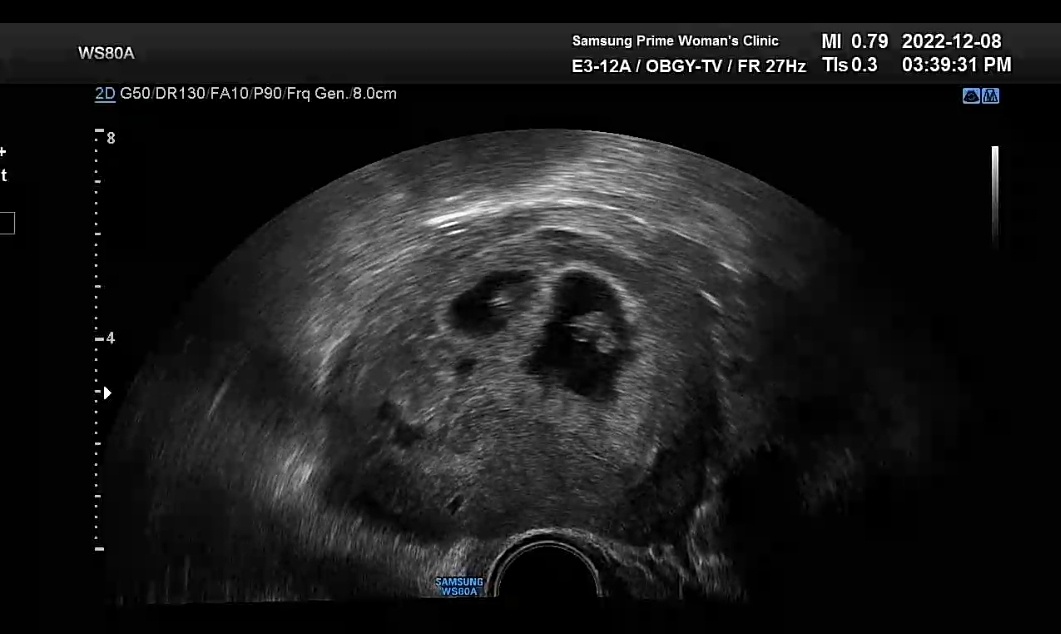

처음엔 인공수정으로 시도를 했었는데 세 차례 다 실패로 끝나서 최종적으로 시험관 시술을 받게 되었는데 첫번째 시험관 시술만에 바로 성공하여 드디어 기다려왔던 임신을 하게 되었다.

난임병원에서 인공수정이나 시험관 시술을 받으면 쌍둥이가 생길 확률이 높다는 말을 예전부터 들어왔었는데 아니나 다를까?

우리에게도 드디어 아기가 찾아왔다!

그것도 둘 씩이나! 쌍둥이로!

시험관 시술 때 35세 이하는 수정된 난자를 2개 넣고 35세 이상은 3개를 넣는다고 한다.

그래서 우리는 35세 이하라 2개를 넣었는데 2개가 다 착상에 성공한 것 같다.